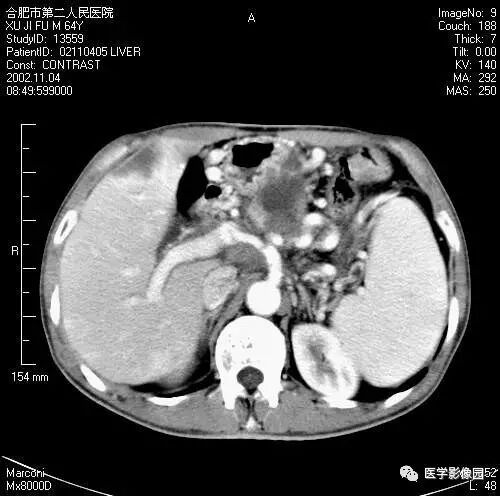

图6-4-10胰腺癌

A.CT平扫胰头球形扩大,

其内呈低密度(↑);

B.增强扫描动脉期,

胰头癌低密度显示更清晰